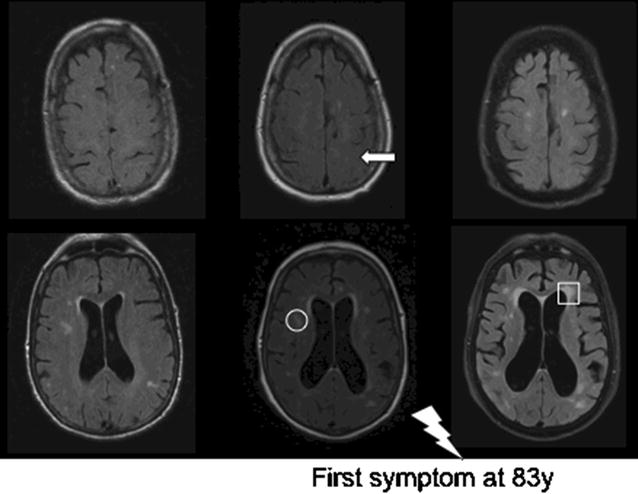

On average the first imaging examination (CT or MRI) was conducted − 6.2 years to symptom onset (range 3.1–10.3). In 2 cases 3 MRIs were available at − 6.1, − 2.8 and 0.2 and − 10.3, − 4.1 and 0.5 years to symptom onset respectively. All time points are relative to symptom onset. Details of the available imaging data are shown in Table 1. An illustrative case (patient 7) with increasing radiological changes from the pre-symptomatic to symptomatic phase is shown in Fig. 1.

| 7 | − 10.3 | MRI | − 4.1 | MRI | − 1.4 | CT | 0.5 | MRI |